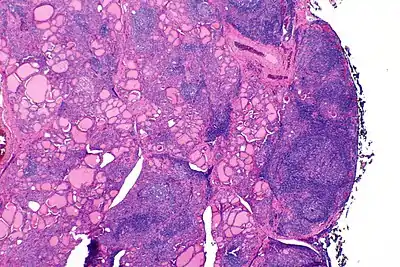

Should any affected organs show chronic inflammatory infiltrate (lymphocytes), this would be an indication. Moreover, autoantibodies reacting to specific antigens is common, in the immune system of an affected individual.[4]